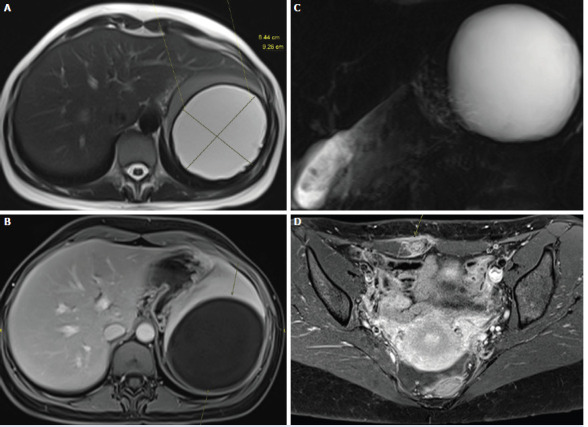

Endometriosis is an estrogen-dependent benign disease that generally affects women at childbearing age. Despite its high incidence, pathogenesis of endometriosis is poorly clarified. There are several theories explaining the mechanism of disease such as retrograde menstruation, coelomic metaplasia, vascular and lymphatic metastasis. While endometriosis has been described in many intra- and extra-abdominal organs including the ovaries, omentum, colon, liver, lungs and brain, parenchymal splenic endometriosis is a rare situation. In recent years, with reported cases, this rare condition came onto the scene. We also wanted to present our case and question the idea of splenic immunity against endometriosis according to current literature. From now on, splenic endometriosis can be thought of as a differential diagnosis for unidentified lesions of spleen.